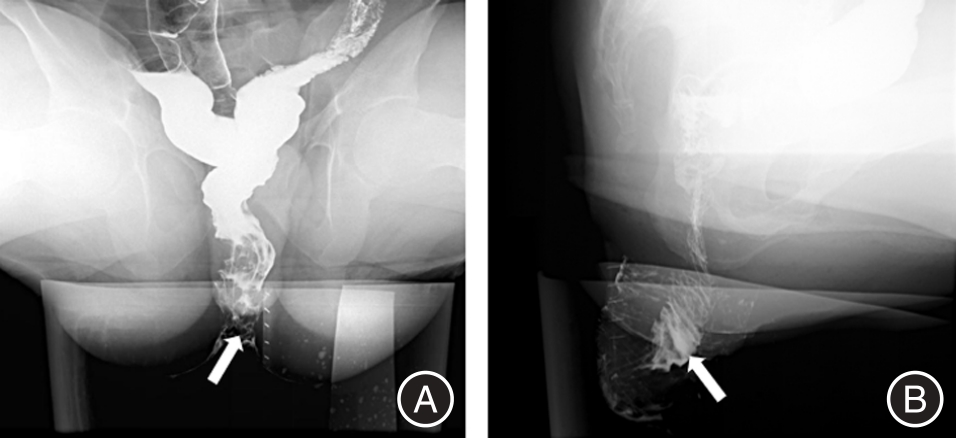

目的 回顾性总结分析孤立性直肠溃疡综合征(SRUS)患者的X线排粪造影(XRD)和MR排粪造影(MRD)的影像学表现,为临床诊疗提供重要信息。 方法 19例经临床、病理和肠镜检查证实的SRUS患者纳入本研究,15例行XRD,7例行MRD,3例患者同时进行了XRD和MRD检查。收集所有患者的数据并进行盆底功能测量。 结果 在XRD结果中,3例(20%)表现直肠内套叠,8例(53.3%)直肠外脱垂,2例(13.3%)中度直肠前突。另外耻骨直肠肌肥厚患者有2例,膀胱脱垂和子宫脱垂患者各有1例。在MRD结果中,3例(42.9%)表现直肠黏膜脱垂(部分性脱垂),4例(57.1%)直肠前突患者中,3例(均为女性)为中度直肠前突,1例为轻度直肠前突。3例患者同时观察到相关的前、中腔室器官下降,2例耻骨直肠肌肥厚,没有患者表现乙状结肠疝。 结论 排粪造影可以评估SRUS患者的直肠外脱垂、直肠前突、直肠黏膜脱垂、直肠内套叠等盆底结构及功能异常,对SRUS患者的治疗具有指导意义。

Objective The imaging findings of X?ray defecography (XRD) and magnetic resonance defecography (MRD) of patients with Solitary Rectal Ulcer syndrome (SRUS) were retrospectively analyzed to provide important information for clinical diagnosis and treatment. Methods 19 patients with SRUS confirmed by clinical, pathological and colonoscopy were included in this study. Among them, 15 patients underwent XRD and 7 patients underwent MRD, and 3 patients underwent both XRD and MRD. Data of all enrolled patients were collected and pelvic floor function was measured. Results In the results of XRD, 3 patients (20%) showed rectal intussusception. 8 patients (53.3%) showed external rectal prolapse and 2 patients (13.3%) showed moderate rectocele. In addition, there were 2 patients of puborectal muscle hypertrophy, and 1 patient of bladder prolapse and uterine prolapse, respectively. For MRD, 3 patients (42.9%) showed rectal mucosal prolapse (partial prolapse). At 4 patients (57.1%) with rectocele, 3 patients (all female) had moderate rectocele, 1 patient had mild rectocele. 3 patients were also observed related anterior and middle compartment organ descent. 2 patients of pubulorectal muscle hypertrophy, no sigmoidocoele. Conclusion Defecography can evaluate the structural and functional abnormalities of pelvic floor in SRUS patients, such as external rectal prolapse, rectal protrusion, rectal mucosal prolapse, and rectal intussusception, which has guiding significance for the treatment of SRUS patients。